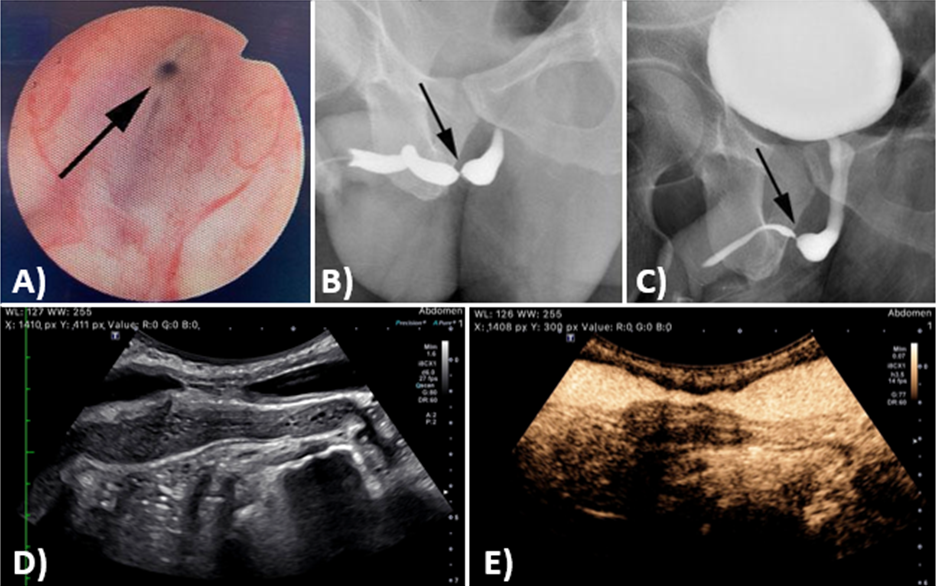

If obstructive voiding symptoms are present, along with a reduced flow rate on uroflowmetry +/- an elevated post-void residual volume on bladder ultrasound, further evaluation of the urethra using imaging modalities is indicated.3 Imaging studies are essential not only to diagnose the stricture, but also to assess the length of the stricture, which can inform operative planning.3,6 A retrograde urethrogram (RUG) and voiding cystourethrogram (VCUG) can be used to view the full length of the urethra.2,6 While VCUG alone is not sufficient to delineate the full male urethra, it can effectively visualize the entire female urethra.3 If VCUG and RUG cannot provide a definitive diagnosis of urethral stricture disease, cystoscopy, also known as urethroscopy, can elucidate the characteristics of a stricture.13 Urethral ultrasound is also an acceptable, though less common, method of evaluating stricture disease. These studies can help identify the stricture and determine its location, length, and severity; with visible narrowing present in the urethral lumen at the site of the stricture (Figure 4 and Figure 5).6

Figure 4: Identification of a urethral stricture using cystoscopy (A), retrograde urethrogram (B), and voiding cystourethrogram (C). Gray-scale ultrasound (D) and contrast-enhanced ultrasound (E) of the urethra can also evaluate stricture disease.

Figures were provided as a courtesy by Dr. Paul H. Chung, Thomas Jefferson University, Philadelphia, PA.

Figure 5: Localization of urethral strictures using retrograde urethrogram. A) Urethrogram from a patient with a bulbar urethral stricture, with the arrowhead indicating the region of interest. B) Urethrogram from a patient with a penile urethral stricture, with the arrowhead indicating the region of interest. C) Urethrogram from a patient with a panurethral stricture.

Figures were provided as a courtesy by Dr. Alex J. Vanni, Lahey Hospital and Medical Center, Burlington, MA.